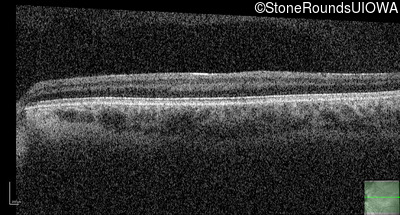

Optical Coherence Tomography - Right - 10/160 sc

Exemplar / OCT Stack

OCT Stack